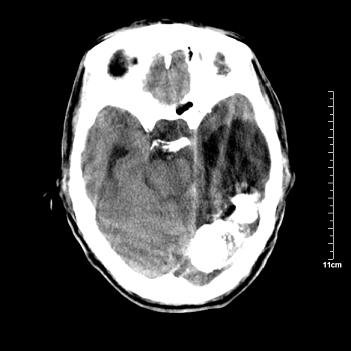

男性患者,72岁,近两天头晕来我院就诊。 因患者血压太高而未做增强,建议病人去市医院做mri检查。等得到mri随访结果再公布给大家。 测及左颞顶枕叶病灶ct值分别为5hu 30hu 729hu。

考虑左侧颞顶枕叶少突胶质细胞瘤。 今天随访患者手术病理结果 病理回报为胶质瘤2级 钙化

左侧颞顶枕叶大片状低密度影,呈均一水样密度,边界清楚,病灶边缘不规则片状钙化,左侧脑室后角扩大,中线结构未见移位,综合来看不像肿瘤,软化灶,钙化不好解释

左侧颞顶枕叶巨大囊性病灶,灶内见小片实性区且灶内及灶周围大量团块状钙化影,灶周水肿少.左侧室枕角内见环形钙化,可见较清晰前壁,钙化与室壁似有间隙.

考虑1寄生虫病2表皮样囊肿钙化3血管畸形,其他不排

今天追踪患者家属手术病理结果 病理回报为胶质瘤2级并钙化

病理回报为胶质瘤2级并钙化